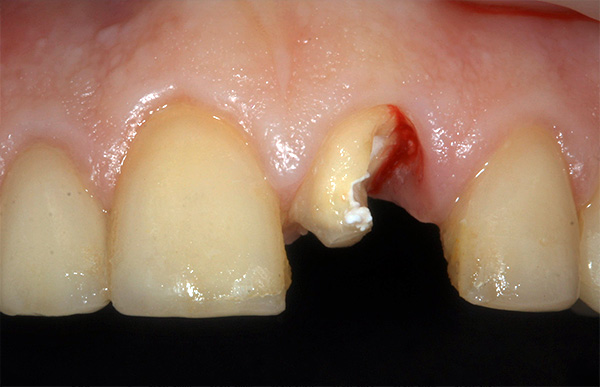

Esta é a situação inicial: a coroa do dente está quebrada quase sob a raiz: